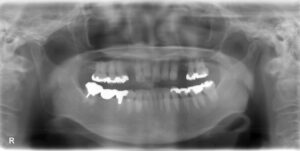

• 上下臼歯5本欠損症例

BEFORE AFTER 74歳女性/上下5本欠損/インプラント埋込手術 【治療内容】 右上第二小臼歯、第一、第二大臼歯…